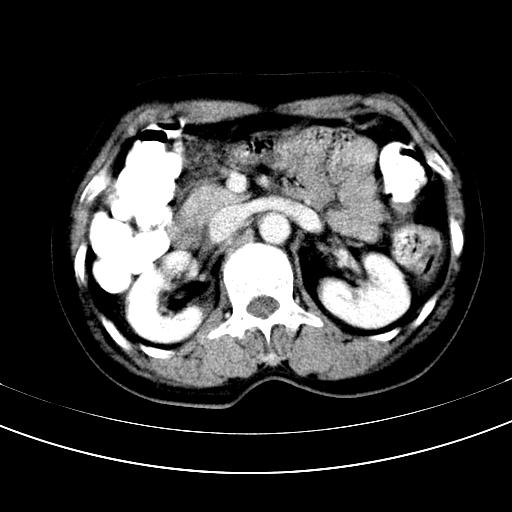

补充强化片

肝左叶及尾叶低密度灶,增强有渐进性明显强化,考虑血管瘤。胃内“充缺”首先要排除异物(食物),变换体位可鉴别。增强时机抓的不好,还应该有延时像。

谢谢楼主的增强片子,平扫没发现左侧肾上腺的问题很不好意思,可惜片子只有门脉期,所以还只有猜,肝脏的病灶在门脉期部分强化,首先考虑为血管瘤(其他的用一种病不好解释)胃要喝水就好了现在不好说是否有问题,左肾上腺的问题考虑是肿瘤。

做了增强后,可以明确胃是没有肿瘤的,肾上腺也没有肿瘤.肝左叶的病灶首先考虑血管瘤,应该再延迟,肝尾状叶的病灶仍不能排除肝癌的可能性.